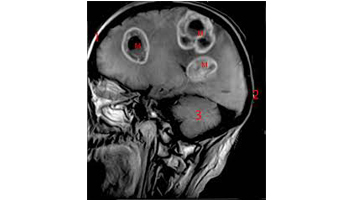

L'imagerie par résonance magnétique (IRM) est une technique d'imagerie médicale permettant d'obtenir des vues 2D ou 3D de l'intérieur du corps de façon non invasive avec une résolution en contraste relativement élevée. L'IRM repose sur le principe de la résonance magnétique nucléaire (RMN) qui utilise les propriétés quantiques des noyaux atomiques pour la spectroscopie en analyse chimique. L'IRM nécessite un champ magnétique puissant et stable produit par un aimant supraconducteur qui crée une magnétisation des tissus par alignement des moments magnétiques de spin. Des champs magnétiques oscillants plus faibles, dits radiofréquence, sont alors appliqués de façon à légèrement modifier cet alignement et produire un phénomène de précession qui donne lieu à un signal électromagnétique mesurable. La spécificité de l'IRM consiste à localiser précisément dans l'espace l'origine de ce signal RMN en appliquant des champs magnétiques non uniformes, des « gradients », qui vont induire des fréquences de précession légèrement différentes en fonction de la position des atomes dans ces gradients.

Il est alors possible de reconstruire une image en deux dimensions puis en trois dimensions de la composition chimique et donc de la nature des tissus biologiques explorés.